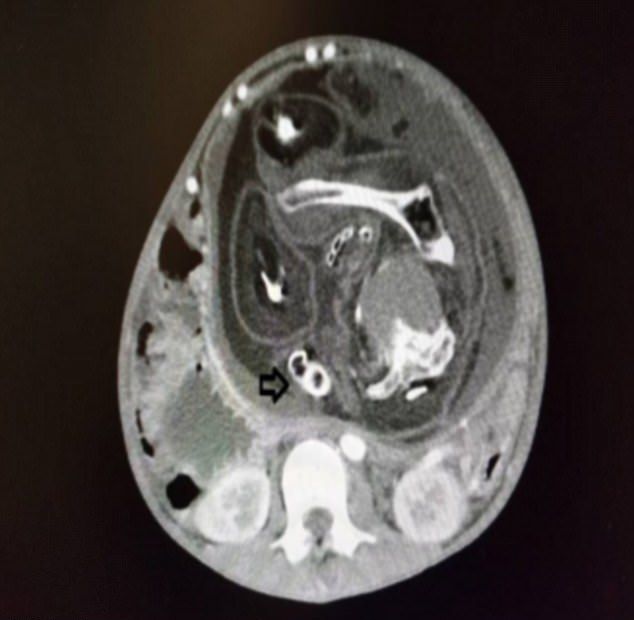

gif_animation マレーシアにて、「お腹が痛い」と病院を訪れた15歳少年の胃の中から摘出された、”本来一緒に生まれてくるはずだった双子(寄生双子)” の体の一部。それは ”髪の毛” と ”男性器” (陰茎)を中心としたモノであった。[2]images